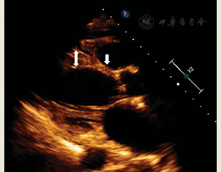

1.超声心动图。经胸超声心动图是疑诊CS患者初筛的首选影像学方法。该法可评估左心室整体收缩功能、左心室几何形状、心肌增厚或变薄部位、舒张期参数及右心室功能。常见的超声心动图异常表现包括局部室壁运动异常、动脉瘤、间隔基底变薄、左心室扩张、左或右心室收缩或舒张功能障碍[18]。然而超声心动图检出CS的灵敏度低,正常结果并不能排除CS。在有心脏症状或心电图异常的结节病患者中,超声心动图的特异性高,若超声心动图表现异常则高度提示CS,其阳性预测值高达92%[19]。

室间隔基底部变薄是CS的特征性表现(图1)。研究发现室间隔变薄(室间隔基底部厚度≤4 mm或室间隔基底部与室间隔比≤0.6)与不良的远期临床转归相关[20]。